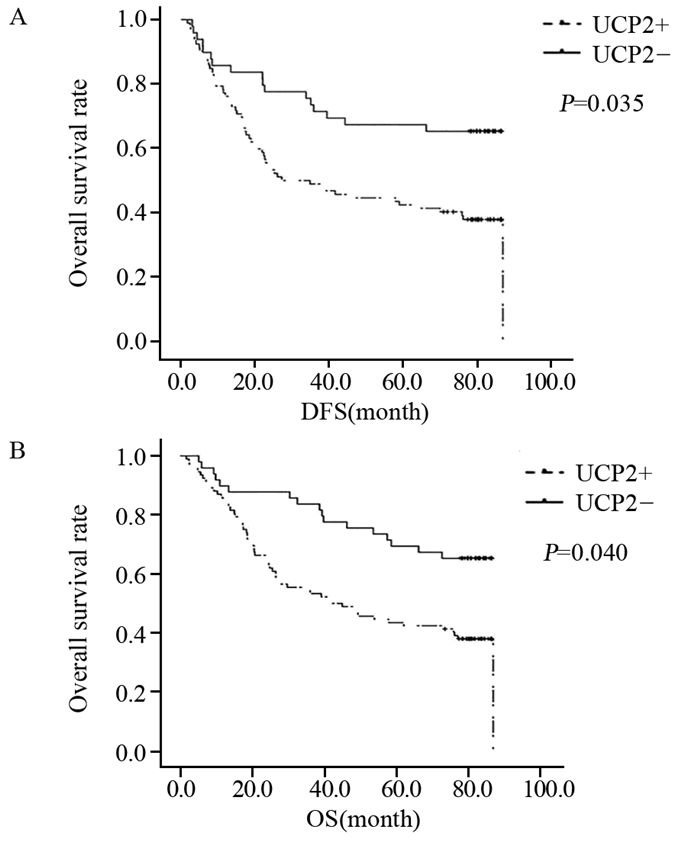

方法免疫组织化学法检测142例胃腺癌及25例癌旁正常胃黏膜组织中UCP2的表达情况,Pearson χ2检验分析其与临床病理特征的关系,Kaplan-Meier法及Cox风险回归模型分析UCP2的表达与胃腺癌患者预后生存的关系。将UCP2 siRNA转染SGC7901胃腺癌细胞系后,Western blot法检测UCP2蛋白的表达,EdU实验检测细胞增殖,划痕实验检测细胞迁移能力。

结果在胃腺癌组织中UCP2蛋白的阳性表达率明显高于癌旁正常胃黏膜组织(P=0.006),UCP2蛋白的表达与肿瘤浸润深度(P=0.024)、TNM分期(P=0.002)、淋巴结转移(P=0.001)显著相关;UCP2阳性患者5年生存率明显低于阴性患者(P=0.001)。在胃腺癌SGC7901细胞系中,UCP2高表达,沉默UCP2的表达能显著抑制肿瘤细胞的增殖,同时降低其迁移能力。

MethodsTotally 142 cases of gastric cancer and randomized 25 cases of normal gastric mucosa tissues in Tianjin Medical University Cancer Institute and Hospital were included. We used immunohistochemical staining to detect the expression of UCP2 and analyze its relationship with clinical pathological features. Kaplan-Meier method and Cox regression analysis were used to explore the correlation between the expression of UCP2 and the survival of gastric cancer patients. Western blot was used to detect UCP2 protein level after UCP2 siRNA transfection into SGC7901 gastric cancer cell lines. EdU assays and scratch assay were used to detect the proliferation and migration abilities.

ResultsThe expression of UCP2 in gastric adenocarcinoma tissues was significantly higher than that in adjacent normal tissues (65.5% vs. 28%, P=0.006). The expression of UCP2 in gastric adenocarcinoma tissues was significantly correlated with tumor infiltration (P=0.024), TNM stage (P=0.002) and lymph node metastasis (P=0.001). The 5-year overall survival of patients with positive UCP2 expression was significantly lower than those without UCP2 expression (P=0.001). Silencing UCP2 expression could significantly inhibit the proliferation and migration abilities of SGC7901 cell lines.